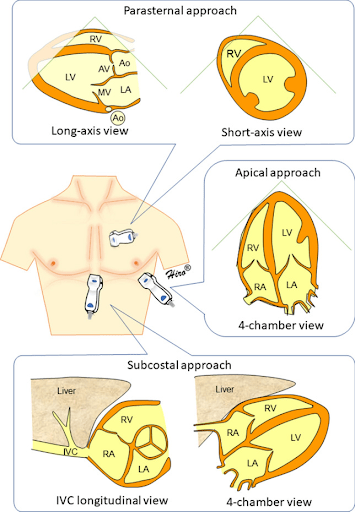

In contemporary primary care, the integration of echocardiography has become a transformative tool for focused cardiovascular assessments such as presence of pericardial effusion, qualitative assessment of ejection fraction, volume status, and evidence of right heart strain. This can help narrow the differential for causes of dyspnea and chest pain using the standard four views: Parasternal Long (PLAX), Parasternal Short (PSAX), Apical 4 Chamber (A4C), and Subxiphoid or Subcostal (SX, SC). In combination with lung ultrasonography, a limited echocardiogram can definitively distinguish between diagnoses such as COPD and CHF exacerbations in minutes.